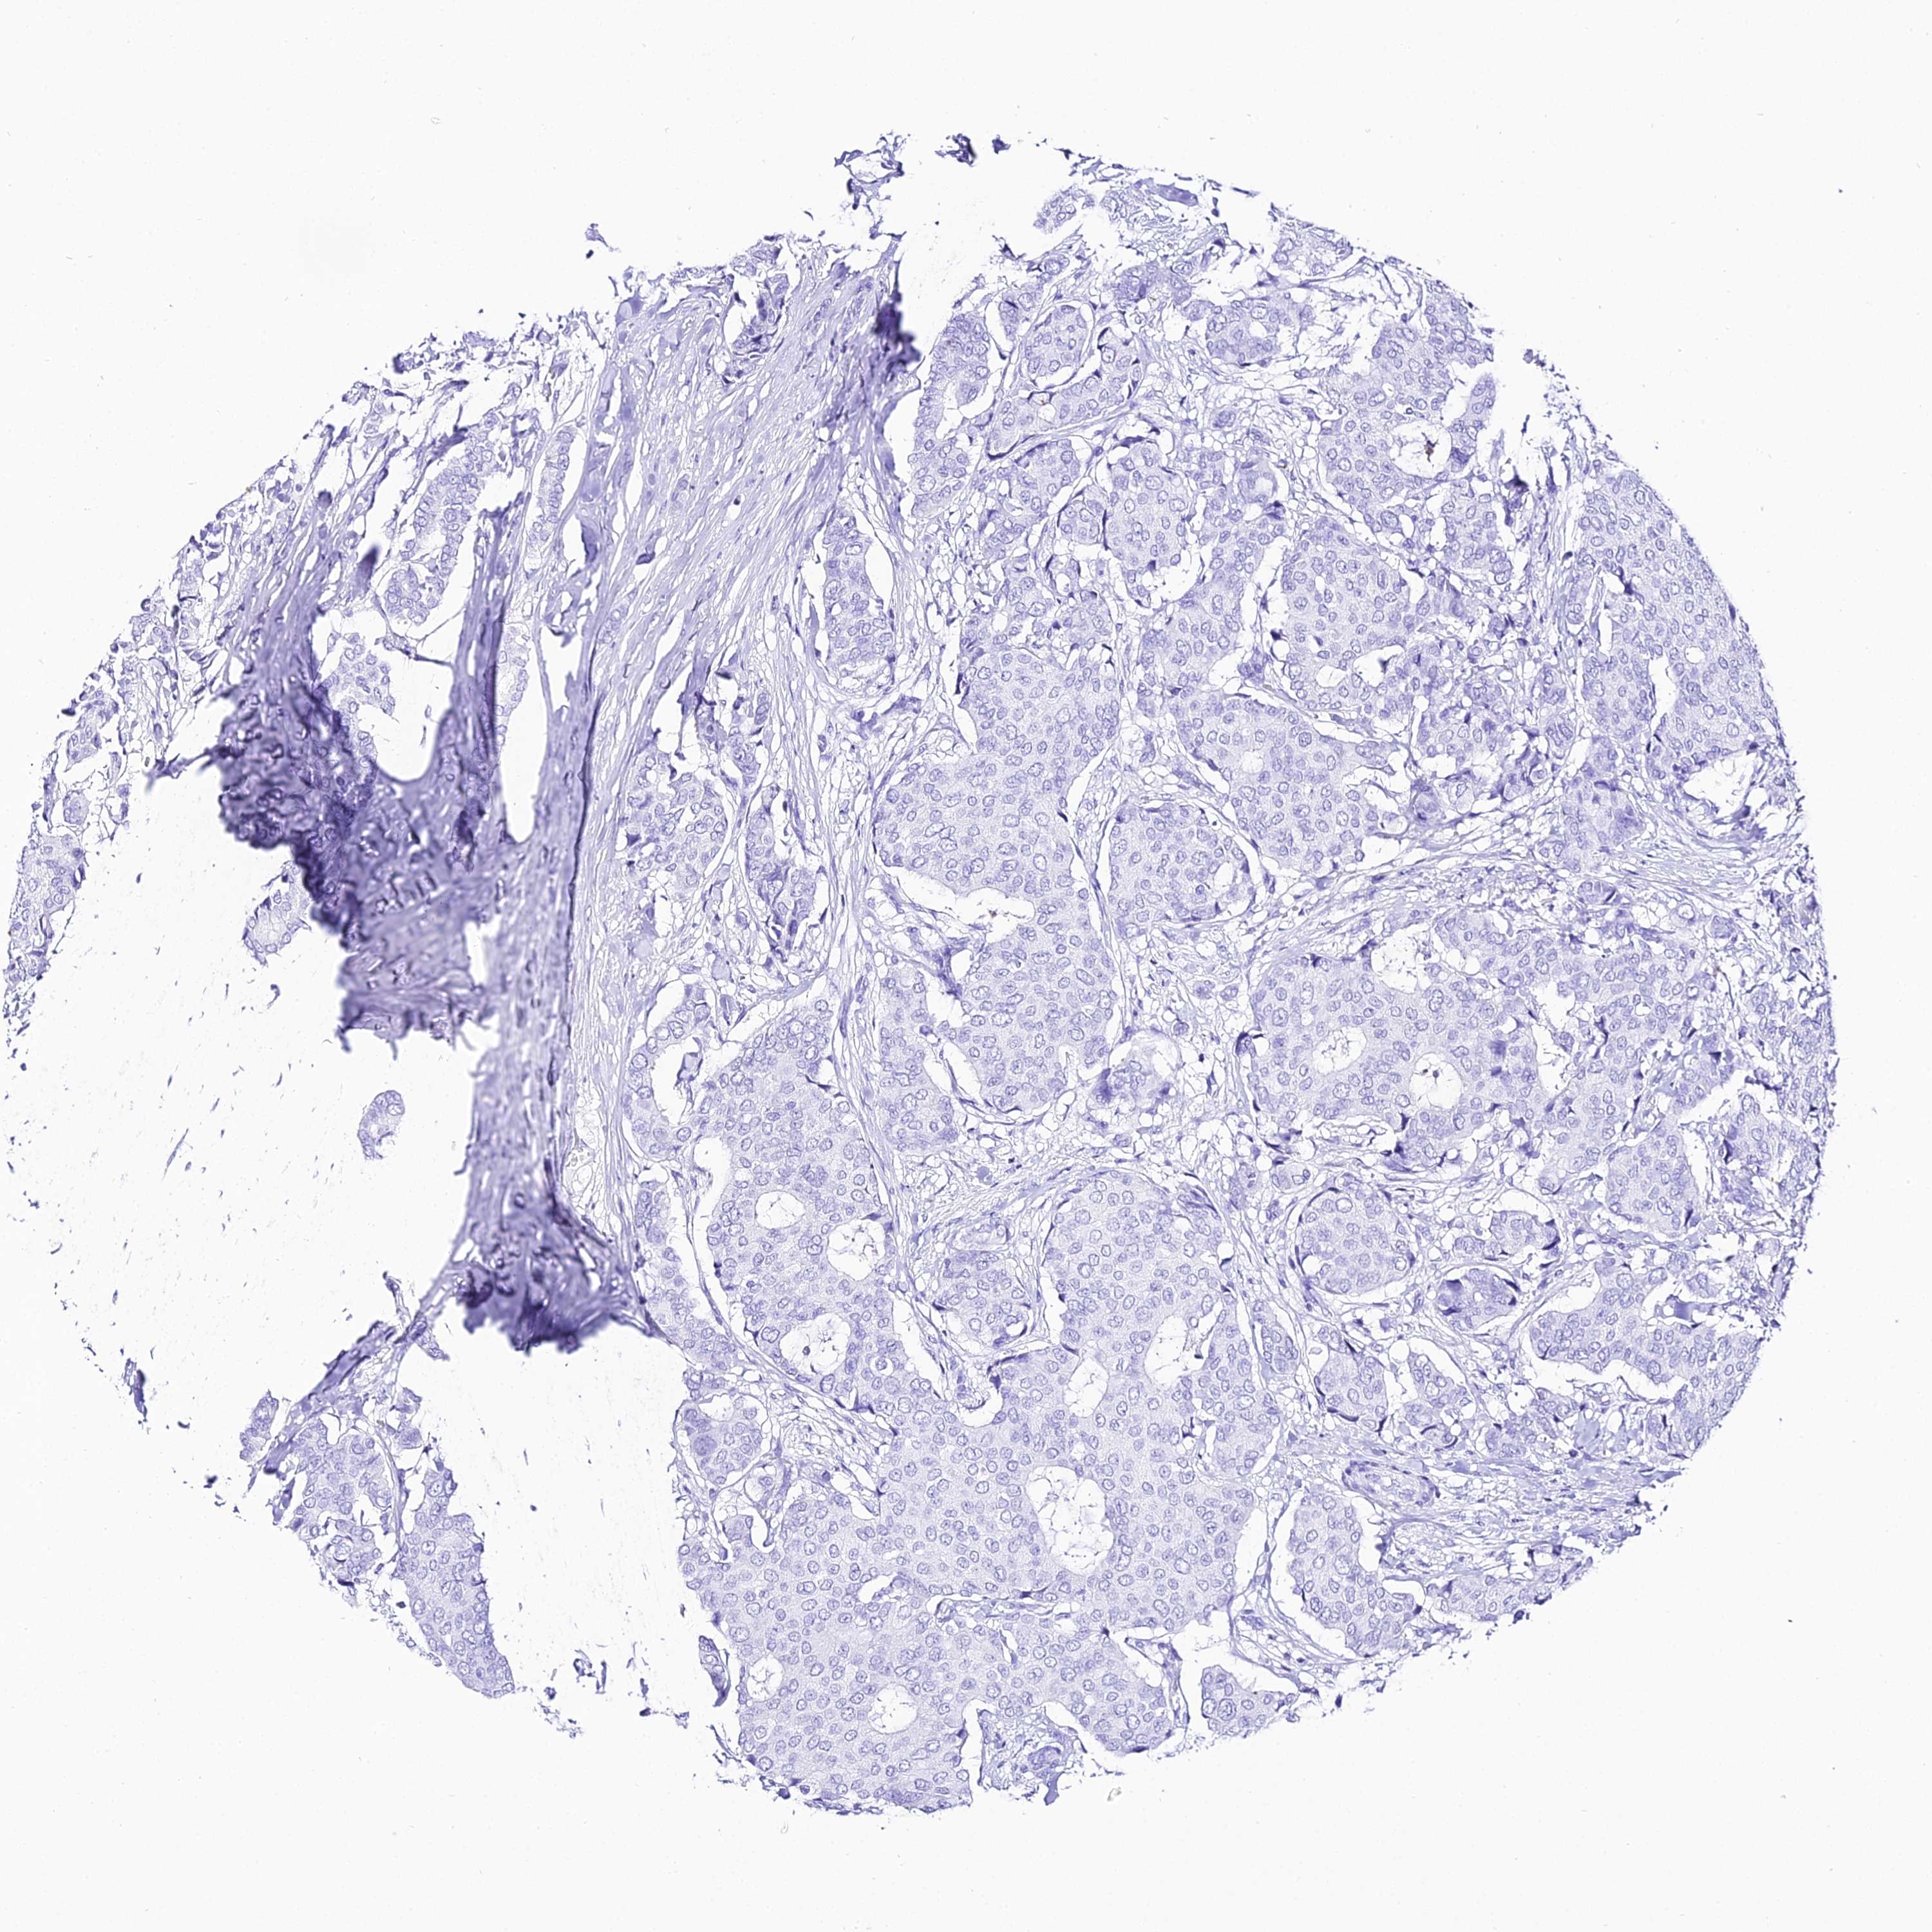

CANCER BREAST CANCER Show tissue menu

Breast cancer

Human cancer